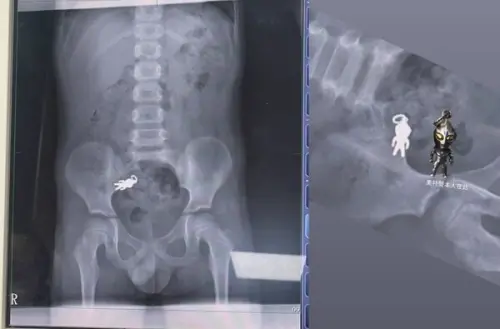

首位合體!7歲童誤吞「超人力霸王」吊飾 X光片畫面曝光網友笑翻

近日宜蘭一名7歲男童,邊看電視邊吃餅乾時不小心將「超人力霸王吊飾」吞下肚,家人緊急帶他到醫院檢查,X光片清楚顯示腹腔內有一個形狀完整的超人力霸王,大小約...